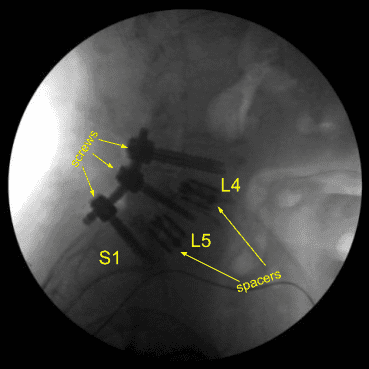

Separadores intersoméricos de titanio expandibles, lordóticos de 15 grados en L5-S1 y lordóticos de 10 grados en L4-5, fueron colocados bajo guía fluoroscópica y ampliados hasta un ajuste adecuado. Hubo un hundimiento parcial del separador intersomático en L5-S1 hacia el cuerpo de L5, pero estaba asegurado y ajustado ajustadamente, y las imágenes mostraron posicionamiento en línea media.

Luego se obtuvo un TAC (mostrado arriba) que mostró la posición correcta de todo el hardware. Las señales de neuromonitorización se mantuvieron estables. La herida fue irrigada abundantemente. Los procesos transversales bilaterales se decorticaron para la artrodesis posterolateral desde L4 hasta S1.

Las varillas de titanio precortadas se perfilaban con curvadores de varilla y se colocaban sobre los tulipanes de tornillo desde L4 hasta S1, y se aseguraban con tapones de bloqueo, todos ellos apretados finalmente con un dispositivo de par y antitorque. Las radiografías AP y laterales finales mostraron una implantación correcta y completa del hardware.